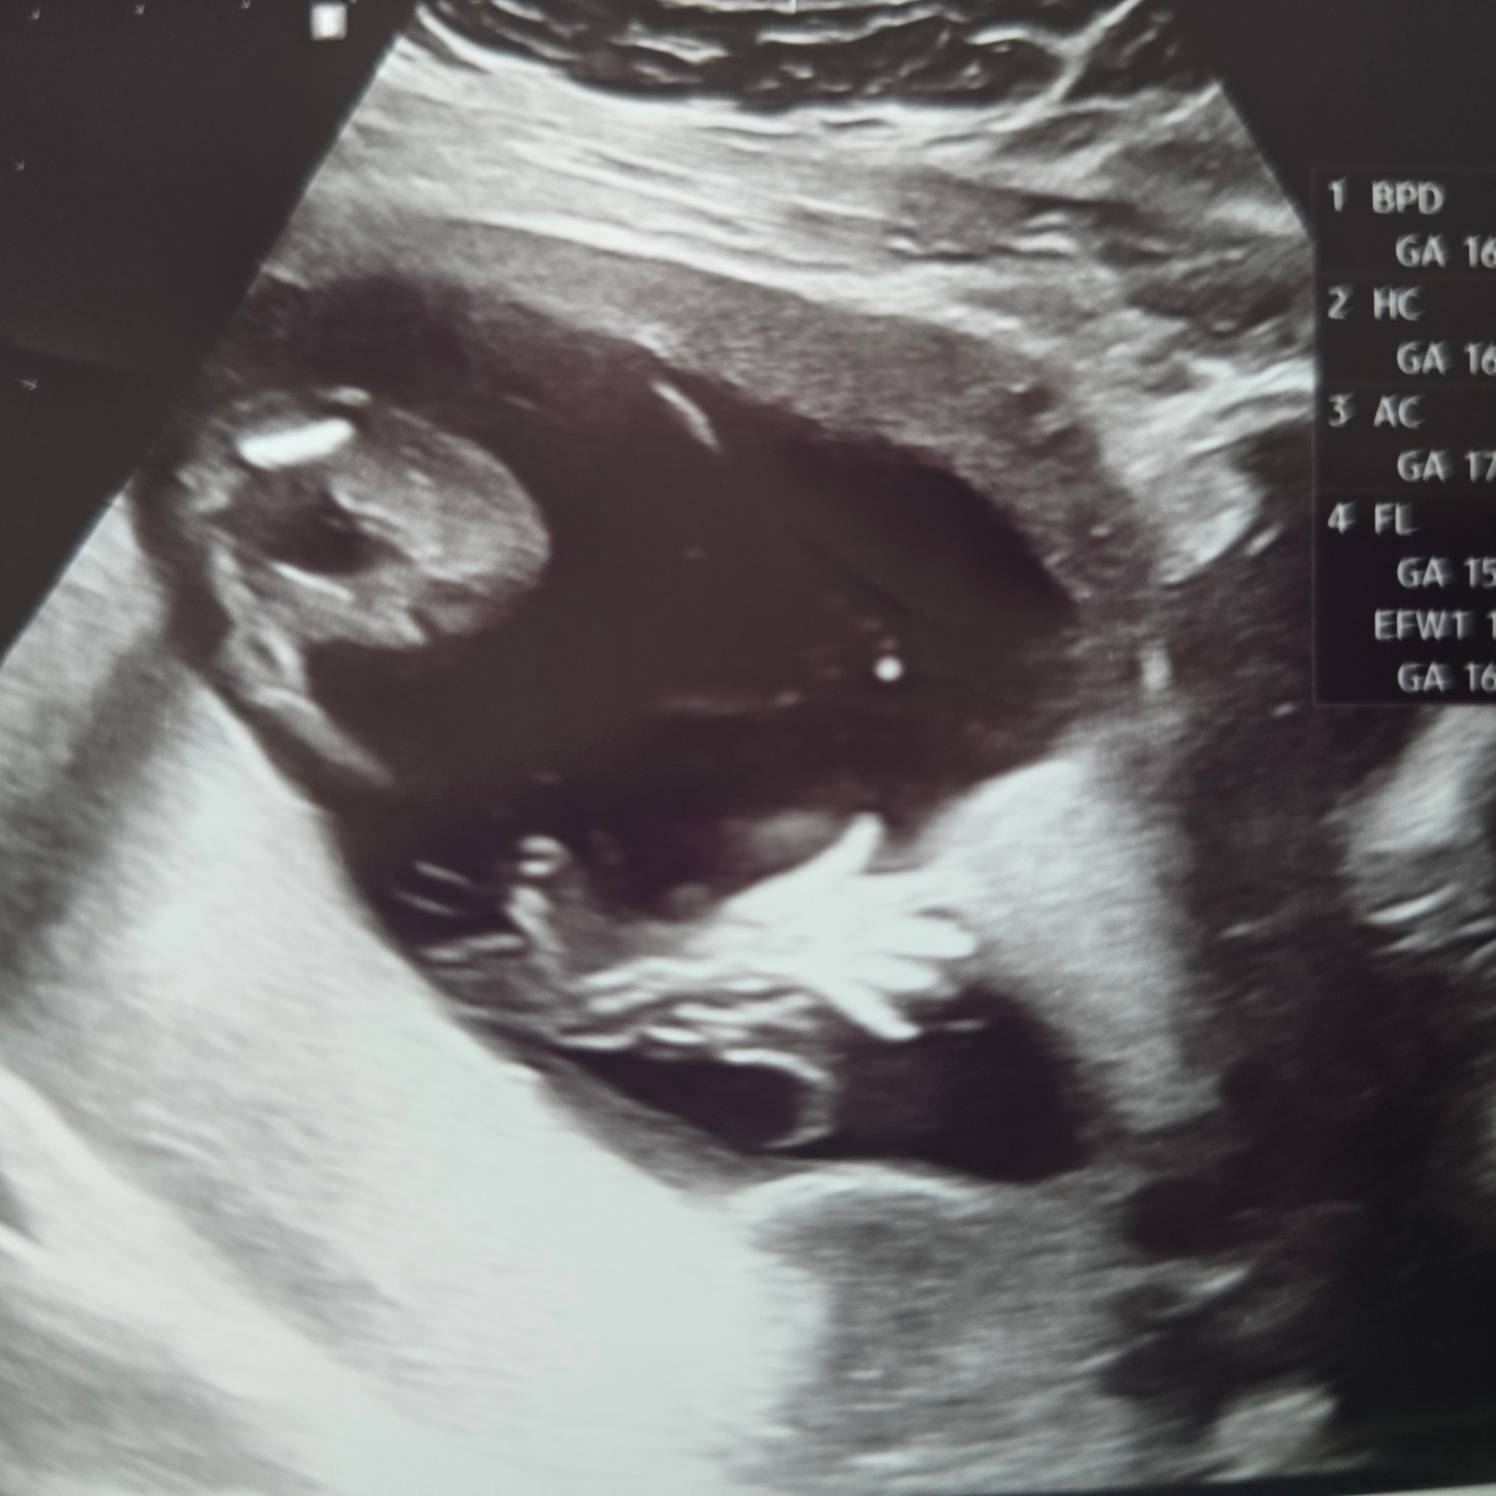

초음파로 만나고 온 뚝딱이는 또 많이 성장해 있었다.ㅎㅎ

엄마아빠 안녕? 인사하듯 손가락을 쫙 피고 보여주며 잘 있다고 인사를 한다.ㅋㅋㅋ

귀여운 뚝딱이를 보니 힘이 난다.ㅎㅎ